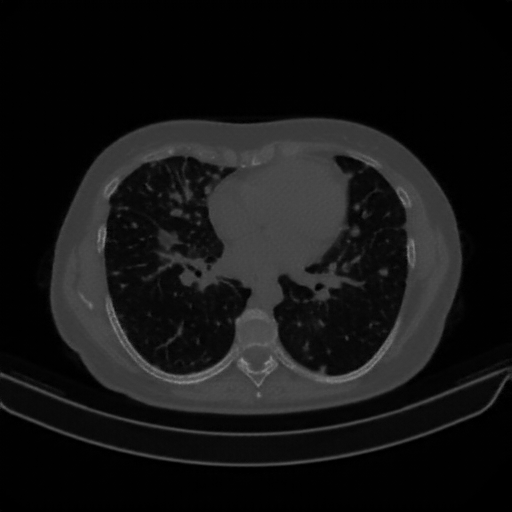

Original NATIVE CT scan (input)

Full window (WL 1023.5, WW 4095 β†’ Low βˆ’1024, High +3071)

Lung window (WL -600, WW 1500 β†’ Low βˆ’1350, High +150)

Mediastinum window (WL 40, WW 400 β†’ Low βˆ’160, High +240)